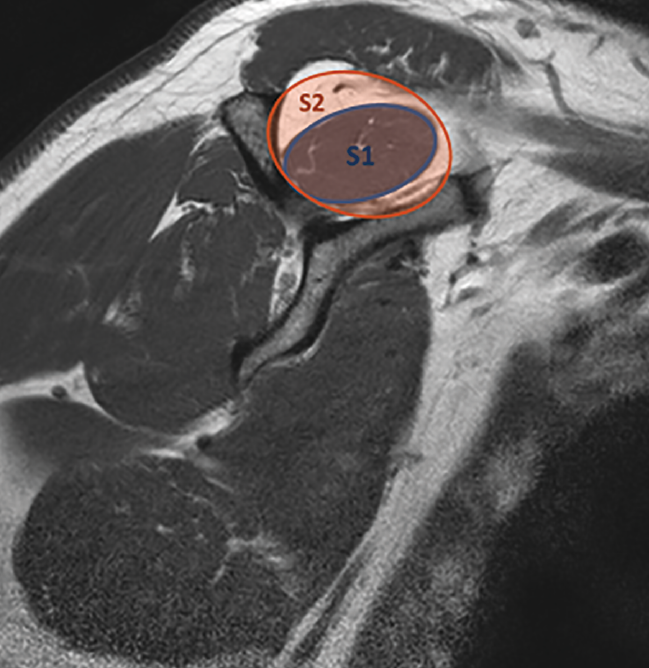

Otro de los parámetros que nos permite evaluar la RM es la degeneración grasa del músculo(37,38). La pérdida de la tensión que sufre el músculo tras la rotura tendinosa desencadena una serie de cambios fisiopatológicos que llevan a la atrofia radial y longitudinal de la fibra muscular, que con el tiempo progresa hacia la fibrosis y la infiltración grasa(39). Recientemente, se publicó que no existía relación entre la neuropatía del supraescapular, presente en un alto porcentaje de roturas crónicas, y la degeneración grasa(40). La infiltración grasa de los músculos del manguito rotador se ha comprobado como un factor de mal pronóstico para su reparabilidad(35,37,38), por lo que es esencial reconocerla y cuantificarla previamente a la cirugía para planificar el tratamiento de elección. Goutallier en 1994(41) estableció un sistema de clasificación basado en el porcentaje de infiltración grasa que presentaban los músculos del manguito rotador mediante tomografía axial computarizada (TAC) y, posteriormente, Fuchs et al.(42) validaron la clasificación para la RM. Zanetti(43) describió el tangent sign, un signo basado en la RM para valorar la atrofia muscular según el cual el músculo supraespinoso en condiciones normales debe sobrepasar una línea desde el borde superior de la espina de la escápula hasta el margen superior de la coracoides en un plano sagital oblicuo; si existe atrofia, el supraespinoso se mantendrá por debajo de dicha línea (Figura 4). Este signo está relacionado con la infiltración grasa(44) y está considerado un buen predictor de la reparabilidad del manguito y su viabilidad(45). Finalmente, Thomazeau(46) describió la ratio de ocupación. Utilizando el mismo plano que Zanetti, calcula la relación entre el área que ocupa el supraespinoso y el área total de la fosa supraespinosa (Figura 5). Una relación inferior al 60% nos indica atrofia muscular. Posteriormente, demostró la correlación entre la atrofia del supraespinoso y el tamaño de la rotura, concluyendo que este signo representaba un factor de mal pronóstico para la rerrotura postoperatoria(47).

Figura 5. Ratio de ocupación de Thomazeau. Relación entre el área de ocupación del músculo supraespinoso (S1, área azul) y el área total de la fosa supraespinosa (S2, área naranja).